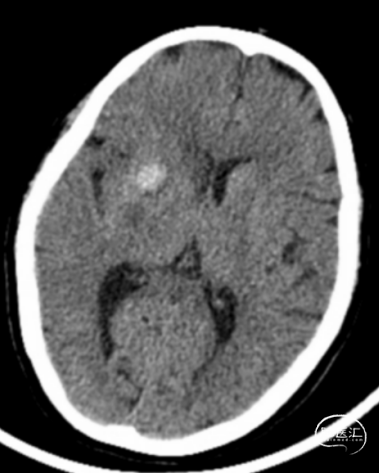

术前CTA+CTP示:1.右侧大脑中动脉M1段闭塞,前交通开放,右侧后交通开放;2.右侧大脑中动脉供血区大面积TTP、MTT延长,CBF降低,CBV减低。

术前头颅CT示:颅内未见明显异常。

术后24小时头颅CT:右侧基底节区少量出血及低密度灶。